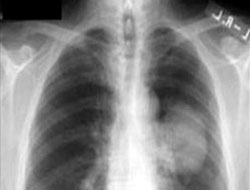

AKCİĞER KANSERİYLE SAVAŞTA YENİ UMUT

Amerikalı bir grup bilim adamı, akciğer kanserinin gelişiminde önemli rol oynadığına inandıkları bir molekül keşfetti.

Kanserde önemli rol oynadığına inanılan bir molekül keşfedildi.